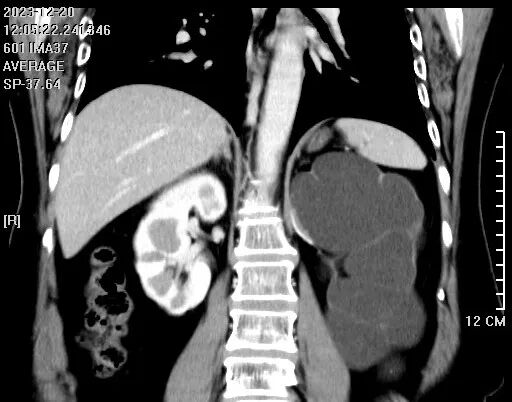

患者左側(cè)輸尿管上段有一個2*3mm小結(jié)石

左腎重度積水腫像個水球,腎皮質(zhì)薄如紙,預(yù)示著它已經(jīng)沒有什么功能了